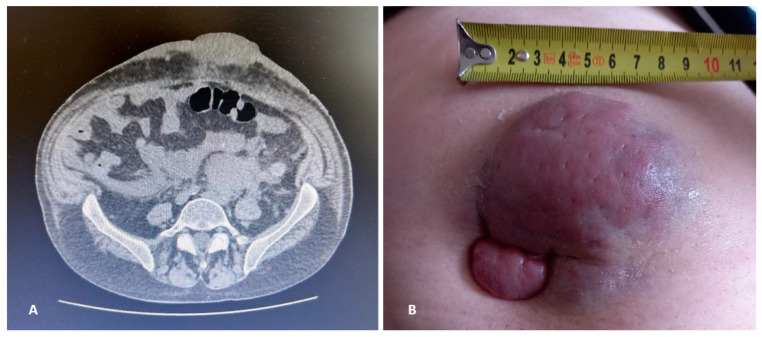

Neoplastic plasma cells (PCs) proliferation at anatomic sites dislocated from the bone marrow (BM) or their contiguous growth from osseous lesions that disrupt the cortical bone is termed extramedullary multiple myeloma (EMD). EMD still remains challenging from a therapeutic and biological perspective. Pathogenesis has not been completely clarified, and it is generally associated with high-risk cytogenetics (HRCAs). In order to emphasize the clinical and biochemical complexity of this disease, we have decided to describe the case of a patient affected by relapsed-refractory (RR) EMD, which presented as para-osseous plasmacytoma with a bi-phenotypical immunoglobulin (Ig) component and lately relapsed as soft-tissue plasmacytoma with a total immunophenotype switch. We have also hypothesized a correlation between Ig patterns and prognosis and suggested the possible inclusion of these biochemical features in the general risk assessment.